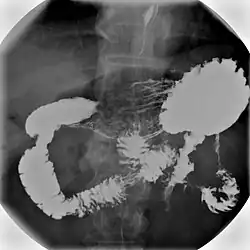

An upper gastrointestinal series, also called a barium swallow, barium study, or barium meal, is a series of radiographs used to examine the gastrointestinal tract for abnormalities. A contrast medium, usually a radiocontrast agent such as barium sulfate mixed with water, is ingested or instilled into the gastrointestinal tract, and X-rays are used to create radiographs of the regions of interest. The barium enhances the visibility of the relevant parts of the gastrointestinal tract by coating the inside wall of the tract and appearing white on the film. This in combination with other plain radiographs allows for the imaging of parts of the upper gastrointestinal tract such as the pharynx, larynx, esophagus, stomach, and small intestine such that the inside wall lining, size, shape, contour, and patency are visible to the examiner. With fluoroscopy, it is also possible to visualize the functional movement of examined organs such as swallowing, peristalsis, or sphincter closure. Depending on the organs to be examined, barium radiographs can be classified into "barium swallow", "barium meal", "barium follow-through", and "enteroclysis" ("small bowel enema"). To further enhance the quality of images, air or gas is sometimes introduced into the gastrointestinal tract in addition to barium, and this procedure is called double-contrast imaging. In this case the gas is referred to as the negative contrast medium. Traditionally the images produced with barium contrast are made with plain-film radiography, but computed tomography is also used in combination with barium contrast, in which case the procedure is called "CT enterography".[1]

Types

Various types of barium X-ray examinations are used to examine different parts of the gastrointestinal tract. These include barium swallow, barium meal, barium follow-through, and barium enema.[2] The barium swallow, barium meal, and barium follow-through are together also called an upper gastrointestinal series (or study), whereas the barium enema is called a lower gastrointestinal series (or study).[3] In upper gastrointestinal series examinations, the barium sulfate is mixed with water and swallowed orally, whereas in the lower gastrointestinal series (barium enema), the barium contrast agent is administered as an enema through a small tube inserted into the rectum.[2]